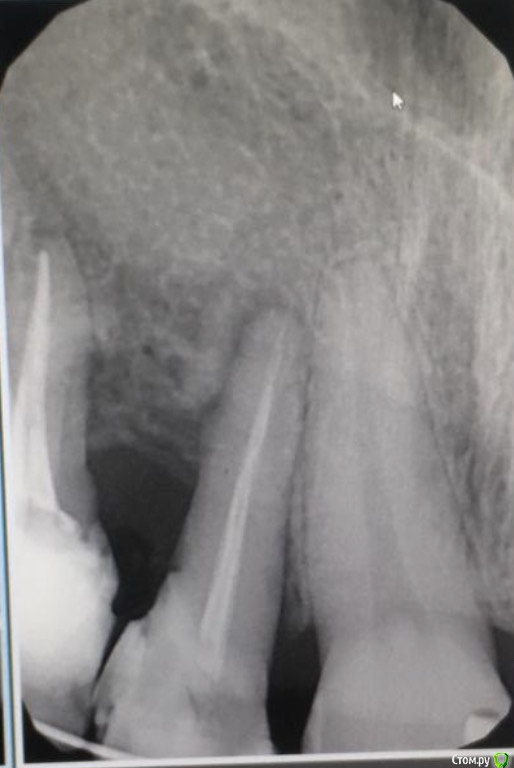

It'sGeorgy Опубликовано 4 июля, 2020 Поделиться Опубликовано 4 июля, 2020 Доброго времени суток!История такая: девушке (примерно 30-35 лет) в детстве был удален клык. После чего она перенесла 2 неудачных ортодонтии. Сейчас находится в процессе 3ьей попытки ортодонтического лечения. Пол года назад ситуация была такая: Сейчас такая: Котэ сделает в теч недели, прикреплю сюда же. Перкуссия 1.2 и 1.4 безболезненна. 1.4 без подвижности, 1.2 с I степенью подвижности. Само собой, как только снимут брекеты подвижность увеличится.Из личных мыслей: попробовать открыть, откюретажить корни, Эмдогейн, большой ССТ с бугра. Жду от этого небольшого прироста кости и "закрытия" кармана, чтобы внутрь перестала попадать пища.Всегда актуальный вариант: удаление обоих, мостовидная конструкция 1.1-1.5. Буду рад любым советам. Ссылка на комментарий